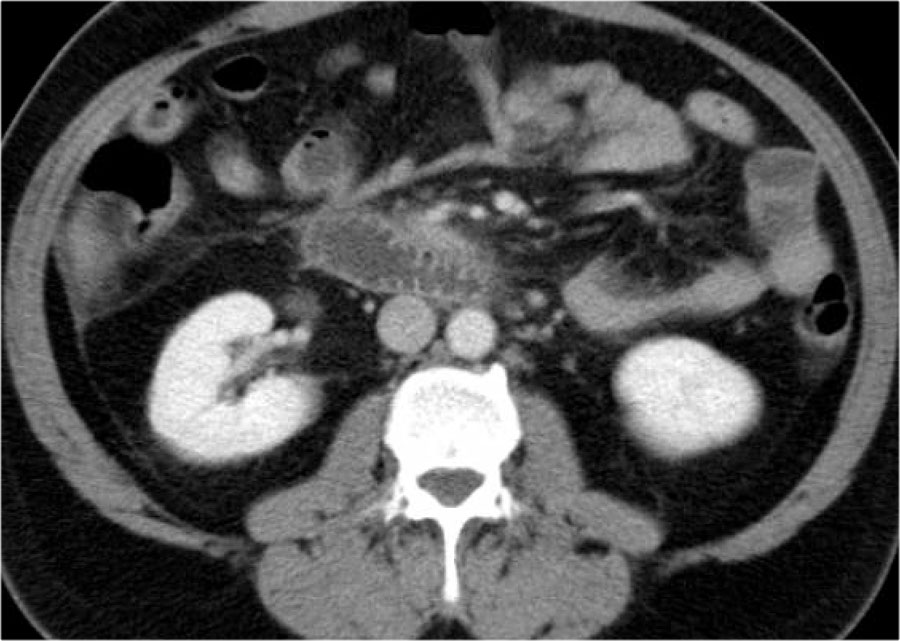

Ở bệnh nhân này, tụy ngấm thuốc bình thường với các ổ hoại tử cấp tính không đồng nhất có vách ngăn xung quanh, có tỷ trọng dịch và mỡ.

Đây có thể là hoại tử mô quanh tụy.

Hai tuần sau, xuất hiện các bóng khí trong ổ dịch quanh tụy, phù hợp với ổ hoại tử cấp tính nhiễm trùng.

Bệnh nhân này được phẫu thuật.

Phẫu thuật viên đã lấy ra một lượng lớn mô hoại tử và ước tính đã cắt bỏ hơn 90% tụy.

Tiếp tục xem hình ảnh tiếp theo.

Đáng chú ý, CT thực hiện 6 tháng sau phẫu thuật cho thấy tụy bình thường.

Điều này cho thấy rằng trong phẫu thuật, việc phân biệt giữa hoại tử nhu mô tụy và hoại tử mô quanh tụy đôi khi là không thể.